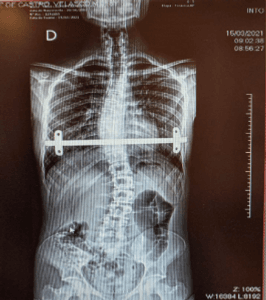

Yago venceu a primeira etapa, que foi a cirurgia para colocação da barra de ferro que paralisou a deformação óssea (Pectus Escavatum) e salvou sua vida. Porém agora ele terá que se submeter a outra cirurgia de alta complexidade para a retirada desta barra metálica que lhe permitirá seguir uma vida normal.